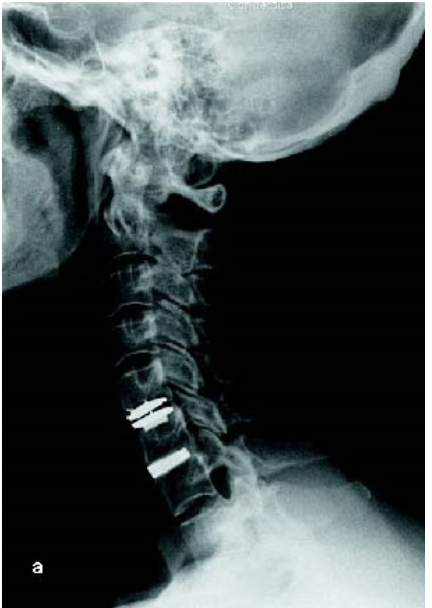

Columna Cervical

Nuestra empresa cuenta con diferentes soluciones para las patologías de columna cervical, tales como: tornillos para fijación de la columna, cage, placas y discos para estabilizar y reemplazo de cuerpo vertebral.